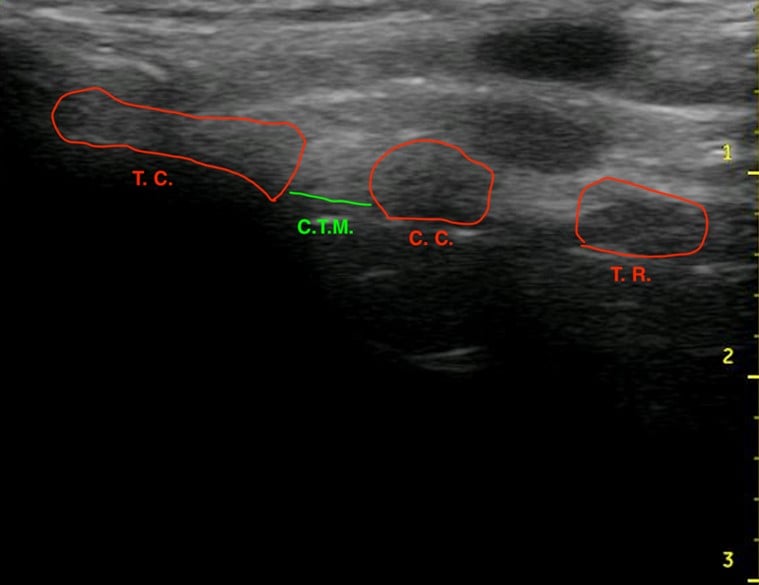

Figure 1.Ultrasound of the midsagittal plane of the anterior neck showing the thyroid cartilage (T.C.), cricothyroid membrane (C.T.M.), cricoid cartilage (C.C.), and the first tracheal ring (T.R.).

EM physicians are familiar with the technique of performing cricothyrotomy after identifying the CTM by palpation. In 2012, Keith Curtis and colleagues described a novel technique of ultrasound-guided, bougie assisted cricothyrotomy in cadavers.7 In this study, operators viewed the laryngeal cartilaginous structures including the CTM with the linear ultrasound transducer in long axis, the CTM was cut with a scalpel under active ultrasound guidance, then the bougie and endotracheal tube (ETT) were passed. This study reported a success rate of 20/21 attempts and an average time to completion of 26.2 seconds. Others have described ultrasound guidance for percutaneous tracheostomy with the probe in a transverse orientation on the neck.8 Ultrasound has been shown to improve localization of the CTM, increase success rate and decrease complications of cricothyrotomy.2,3,9

In contrast to native cartilage, which is hypoechoic with posterior shadowing, the plastic model of the thyroid cartilage and cricoid cartilage appear hyperechoic with more dense posterior shadowing (below). This model performs well as an ultrasound-guided cric training model. It has realistic anatomy. It models a patient with difficult to palpate anatomy, which are patient who may be difficult to intubate and may be more likely to need cricothyrotomy in the first place. The overlying skin and pre-tracheal ballistic gel can be easily and quickly replaced for the next operator in a training setting. The model allows for performing all the steps of cricothyrotomy including passing the bougie and ETT. The model is durable and re-usable.